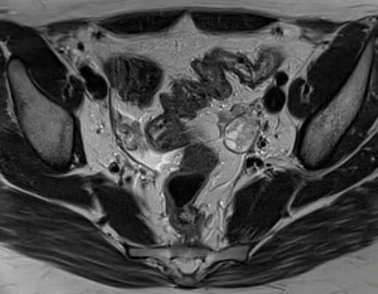

Pelvis : Caractérisation des masses annexielles de l'abdomen aigu à l'incidentalome

Imagerie de la femme